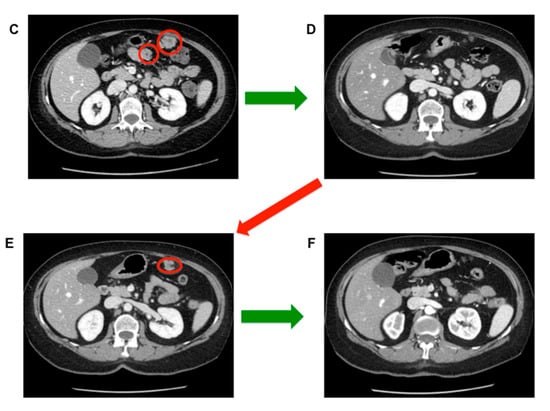

- Stacchiotti, S.; Pantaleo, M.A.; Astolfi, A.; Dagrada, P.; Negri, T.; Dei Tos, A.P.; Indio, V.; Morosi, C.; Gronchi, A.; Colombo, C.; et al. Activity of sunitinib in extraskeletal myxoid condrosarcoma. Eur. J. Cancer 2014, 50, 1657–1664. [Google Scholar] [CrossRef]

- Stacchiotti, S.; Dagrada, G.P.; Morosi, C.; Negri, T.; Romanini, A.; Pilotti, S.; Gronchi, A.; Casali, P.G. Extraskeletal myxoid condrosarcoma: Tumor response to sunitinib. Clin. Sarcoma Res. 2012, 2, 22. [Google Scholar] [CrossRef] [PubMed]